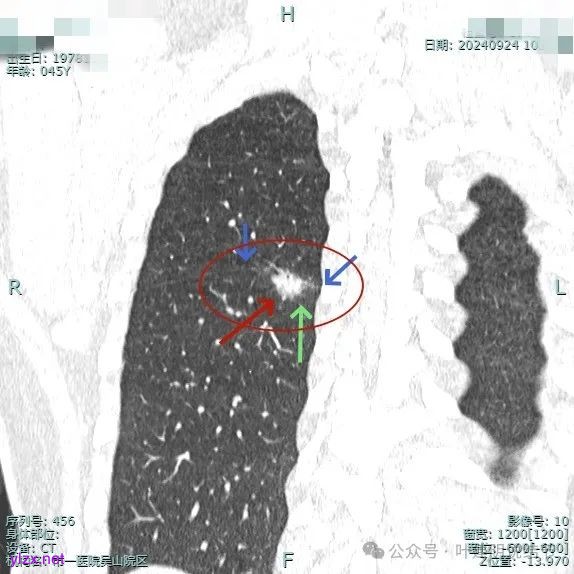

我们先来看2024年9月时的影像:

病灶2:

右中叶内侧段可见混合密度结节,大部分实性,形态与下叶背段的类似。

病灶1:

病灶是混合密度,边缘少许淡磨玻璃,灶内不太致密,表面不平,血管征有,但说不上明显异常增粗。

病灶紧贴叶间裂,而且感觉跨过肺叶,部分影响到上叶了,病灶本身密度虽实性为主,但是不太致密,有点松散的感觉。

总体实性部分密度较高,而磨玻璃部分密度较低,且瘤肺边界欠清,关键是跨叶间裂生长,这与肿瘤似乎不容易解释些。

毛刺有但不太锐利,磨玻璃有但偏淡,实性为但不太致密,叶间裂与之关系密切,病灶跨叶生长。

上图显得与肿瘤较为符合,但跨叶生长的话,侵袭力应该较强,可她这病灶较刚发现时进展并不太明显。

上图层面也较符合恶性,血管进入明显,有浅分叶的样子,整体觉得有一定收缩力与膨胀感。

病灶表面不平,混合密度,磨玻璃成分较淡。